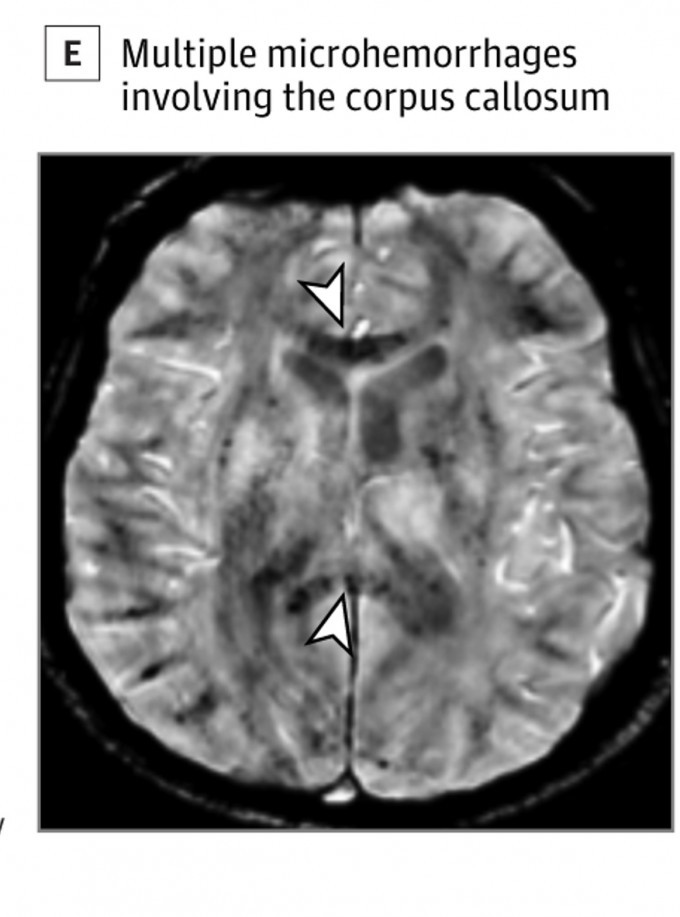

프랑스 파리뇌연구소 연구팀은 이달 15일(현지시간) 신종 코로나바이러스 감염증(코로나19)에 감염됐다가 완치된 57명의 뇌를 자기공명영상(MRI)으로 찍은 모습을 공개했다. 연구팀이 촬영한 영상은 코로나19에 감염됐을 당시 섬망(일시적 환각) 증상을 보인 환자들 가운데 완치된 사람들의 뇌를 촬영한 것이다. 연구팀은 영상 분석 결과 MRI를 촬영한 57명 가운데 41명의 뇌에서 괴사 증상이 일어나는 허혈성 병변과 관류 이상, 미세 출혈 흔적이 나타났다고 밝혔다. 코로나19가 뇌를 공격한 흔적이다.

코로나19 감염 된 이후 섬망 증상을 겪는 환자들의 뇌를 살펴봤더니 미세출혈이 발견됐다. 프랑스 파리뇌연구소 제공